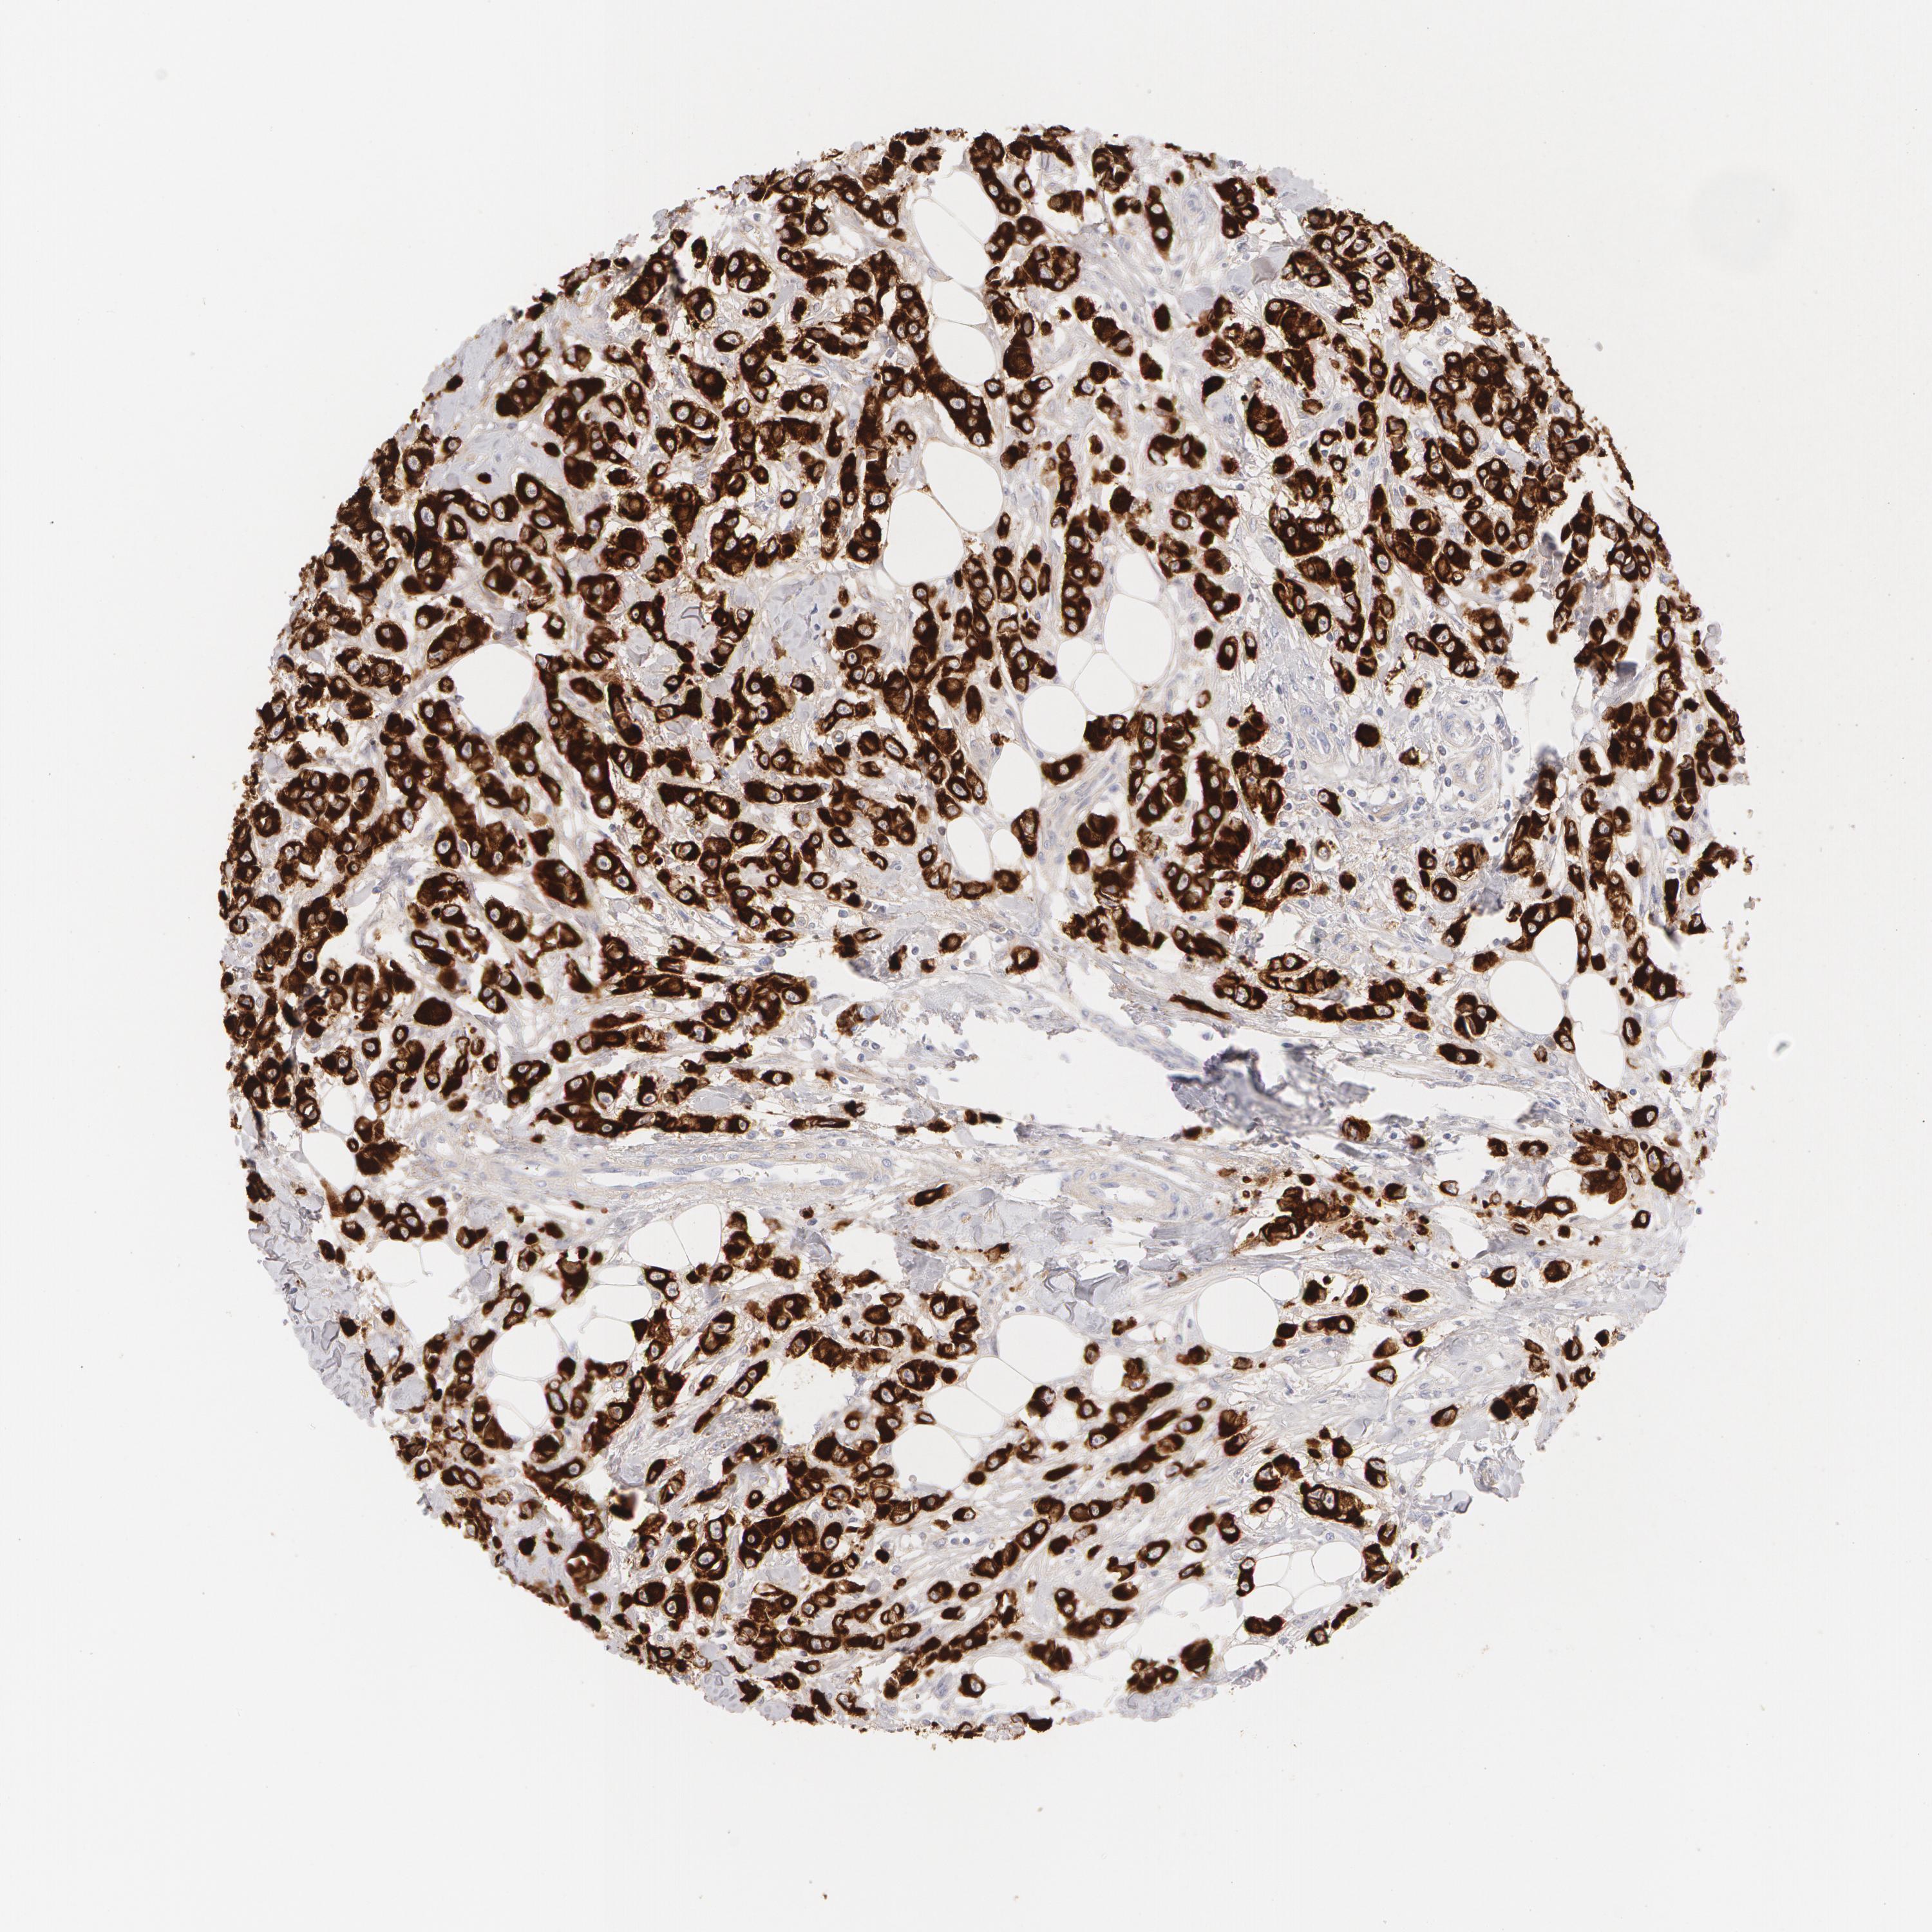

BRCA TCGA BRCA VALIDATION PROTEIN EXPRESSION

ANTIBODIES

AND

VALIDATION